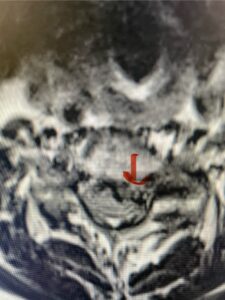

This 61-year-old female with a history of severe osteoporosis and a prior history of a laminectomy from l2-S1 with an L5-S1 instrumented fusion, presents with progressive low back pain and right lower extremity radiculopathy. MRI revealed a grade 1 L2-3 spondylolisthesis with severe stenosis mainly from severe right L2-3 facet joint hypertrophy which was compressing the right L3 descending nerve root. (Fig. 1). She had failed conservative management consisting of physical therapy and pain management with epidurals. She underwent an L1-3 revision laminectomy where we had to dissect a plane underneath the inferior aspect of the L2 lamina. We performed an instrumented fusion at L2-3 with special hydroxyapatite-coated screws to improve fixation to surrounding bone given here severe osteoporosis (Fig. 2) This worked out well and the patient had an uneventful recovery with relief of her leg pain.

Figures 1a: Sagittal and axial T2-weighted lumbar MRIs demonstrating a grade 1 L2-3 spondylolisthesis (red arrow) with severe stenosis secondary to right L2-3 facet hypertrophy (red arrow).